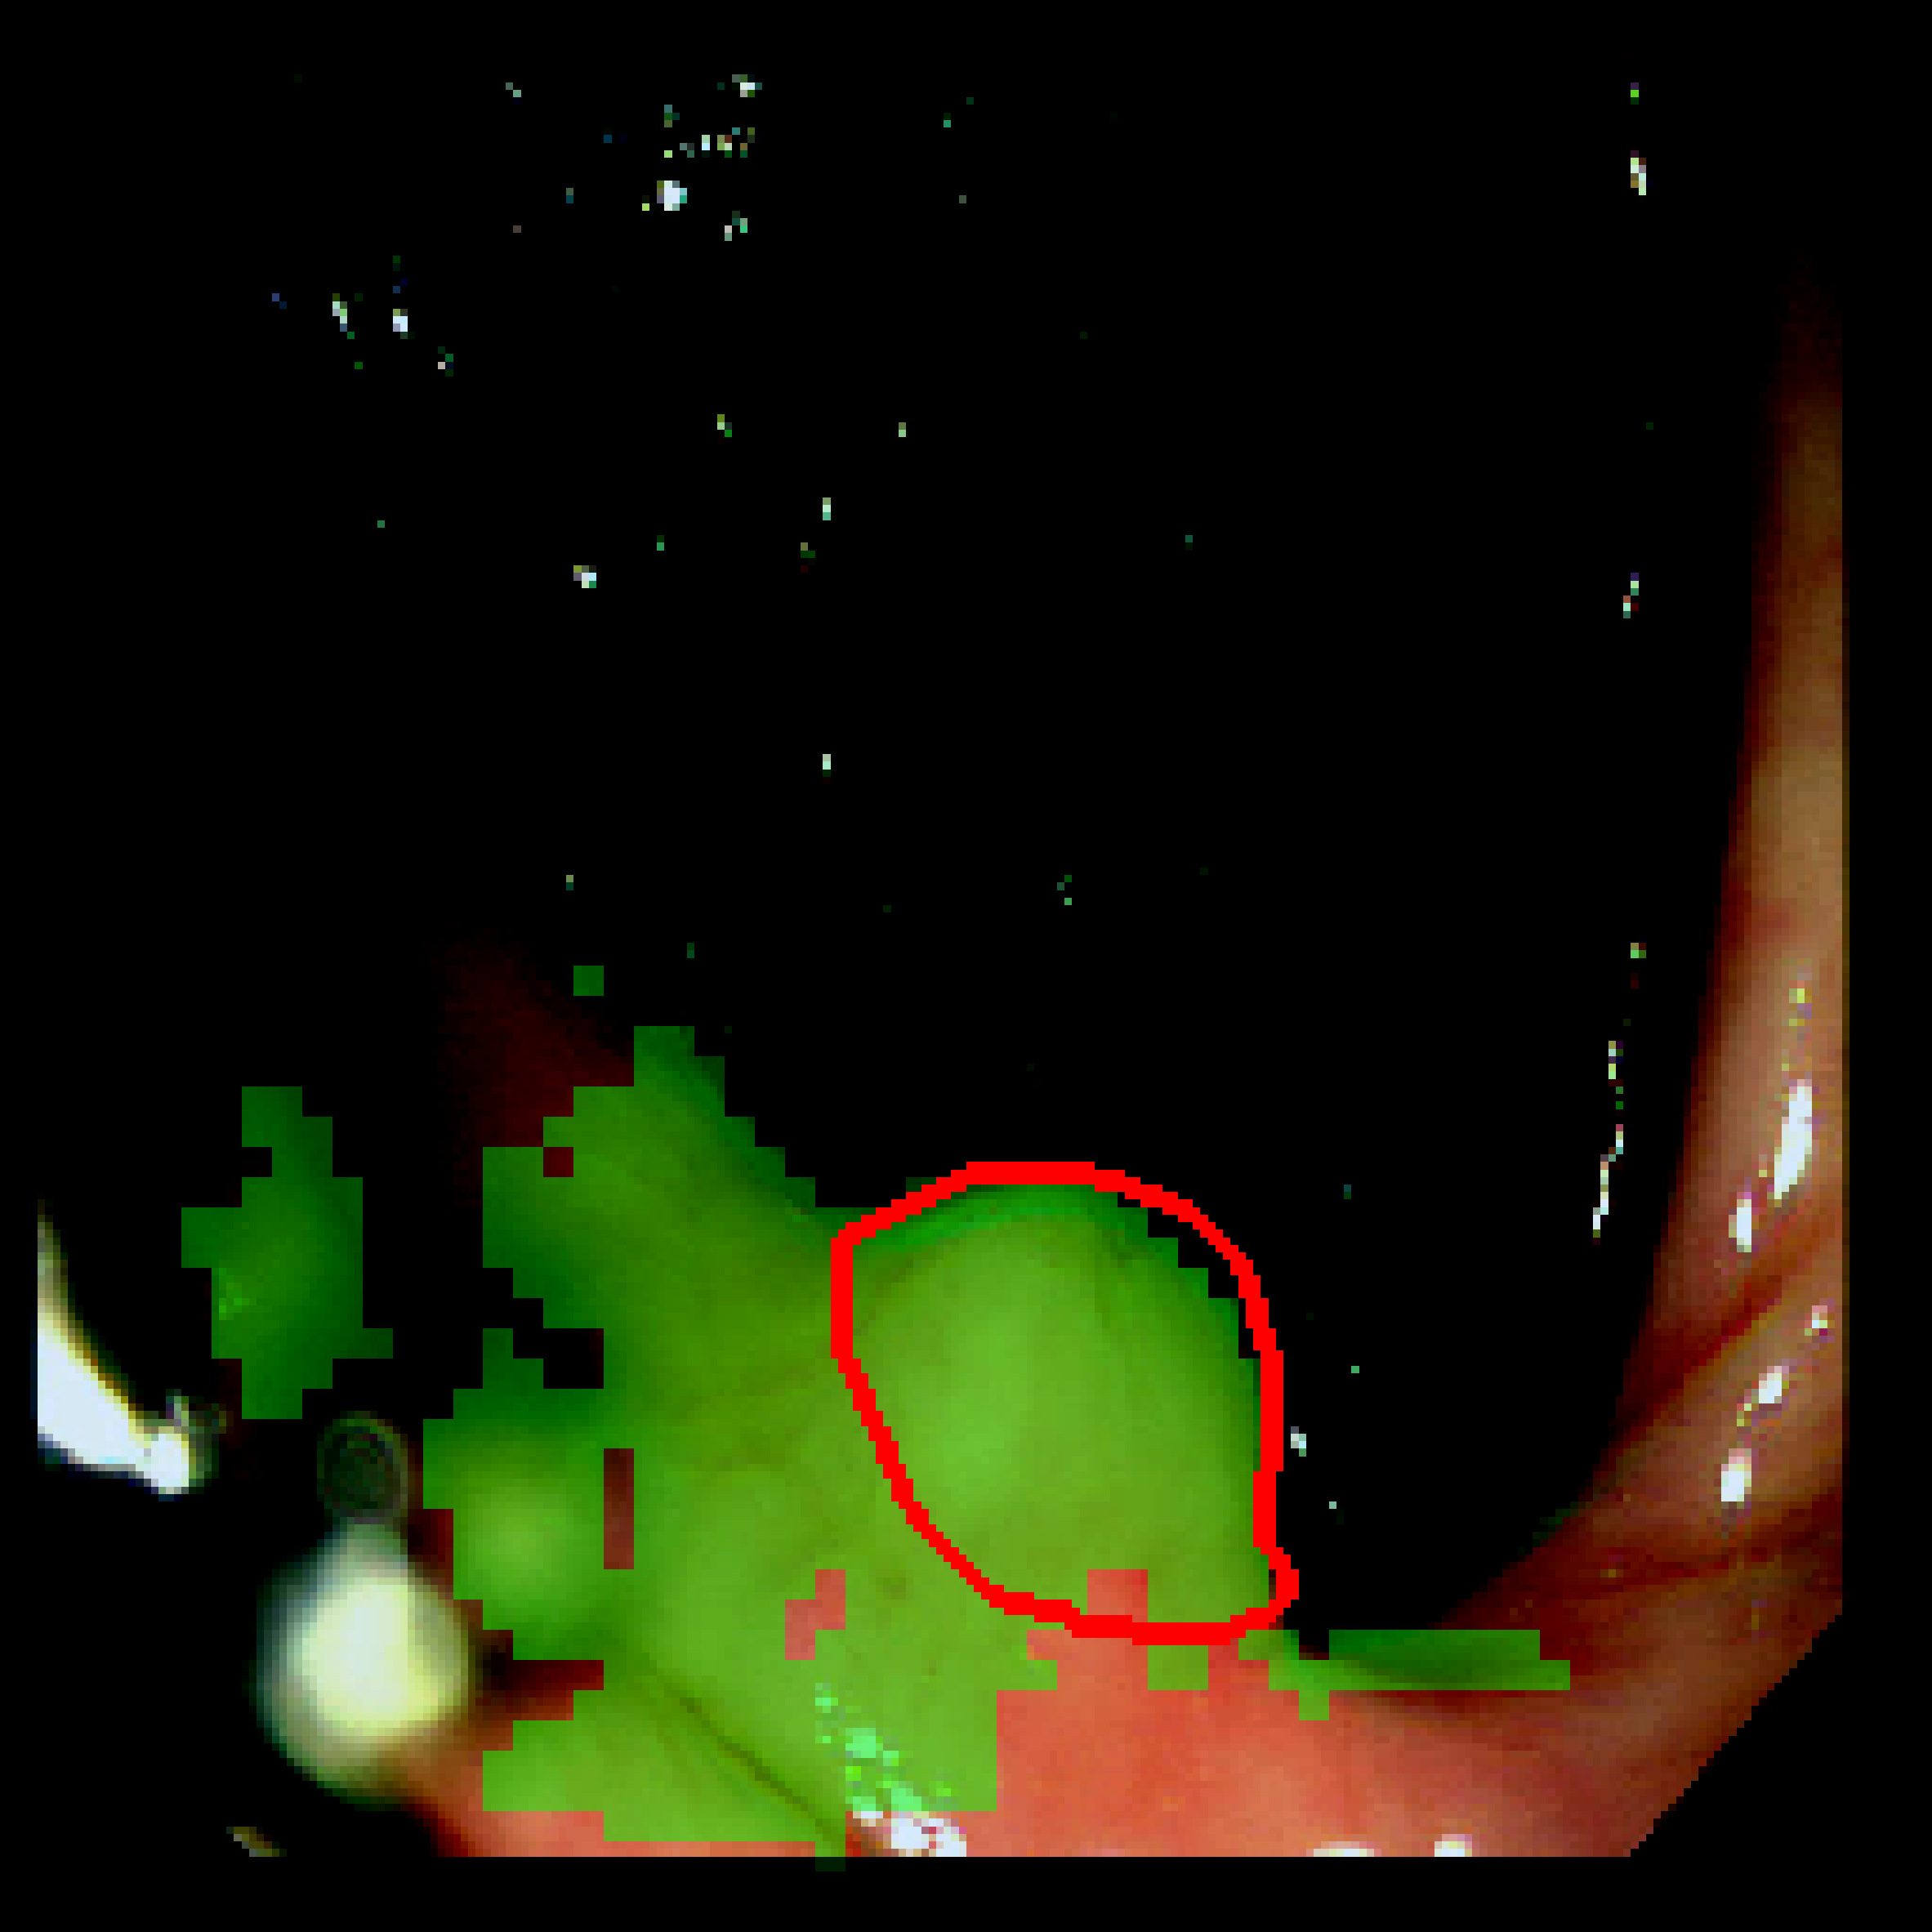

3.3 Qualitative results

Table 3: Qualitative results of different methods, \Circle and \CIRCLE denote groundtruth and predicted mask, respectively.

SAM MedSAM SAM-Med2D CPC-SAM KnowSAM Ours

5% Promise [Uncaptioned image] [Uncaptioned image] [Uncaptioned image] [Uncaptioned image] [Uncaptioned image] [Uncaptioned image]

10% Promise [Uncaptioned image] [Uncaptioned image] [Uncaptioned image] [Uncaptioned image] [Uncaptioned image] [Uncaptioned image]

5% Colon [Uncaptioned image] [Uncaptioned image] [Uncaptioned image] [Uncaptioned image] [Uncaptioned image] [Uncaptioned image]

10% Colon [Uncaptioned image] [Uncaptioned image] [Uncaptioned image] [Uncaptioned image] [Uncaptioned image] [Uncaptioned image]

For the qualitative results shown in Tab. 3, our method consistently produces more accurate and compact segmentation results for most cases in the PROMISE12 and COLON datasets, effectively capturing the prostate and polyp boundaries while suppressing background noise. In contrast, other approaches tend to over-segment the target regions, leading to the inclusion of irrelevant surrounding tissues. These results visually demonstrate the robustness of our method in handling diverse anatomical variations.